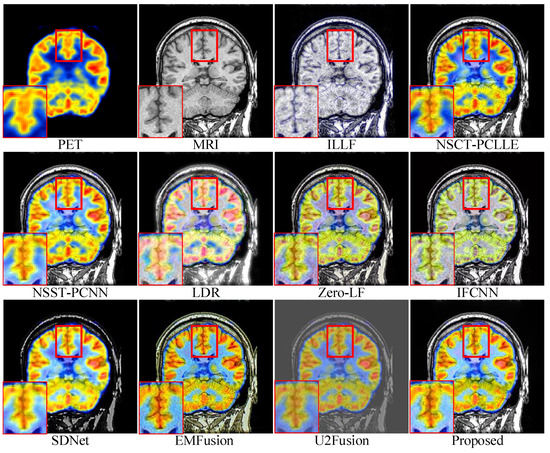

4.3. Subjective Quality Assessment

| Objective evaluation of different fused images in Figure 7 | ILLF | 0.5339 | 0.8063 | 0.2813 | 0.2664 | 5.8953 | 0.1818 |

| NSST-PCNN | 0.6030 | 0.8073 | 1.0805(3) | 0.3283 | 6.0048(2) | 0.3171 | |

| NSCT-PCLLE | 0.5940 | 0.8072 | 1.0262 | 0.3452(3) | 5.9899(3) | 0.3561(2) | |

| LRD | 0.6423 | 0.8081 | 0.7759 | 0.3395 | 6.1174 | 0.3051 | |

| Zero-LF | 0.6972(3) | 0.8087(3) | 1.3326(2) | 0.3233 | 5.7236 | 0.2191 | |

| IFCNN | 0.5995 | 0.8069 | 0.5536 | 0.3206 | 5.6857 | 0.2846 | |

| SDNet | 0.6525 | 0.8074 | 0.2431 | 0.2395 | 5.6691 | 0.2214 | |

| EMFusion | 0.7402(2) | 0.8102(2) | 0.6409 | 0.5500 | 5.6414 | 0.3927 | |

| U2Fusion | 0.5883 | 0.8063 | 0.2151 | 0.2791 | 5.2268 | 0.3342(3) | |

| Proposed | 0.8526 | 0.8132 | 1.4879 | 0.4283(2) | 5.9386(4) | 0.3226(4) | |